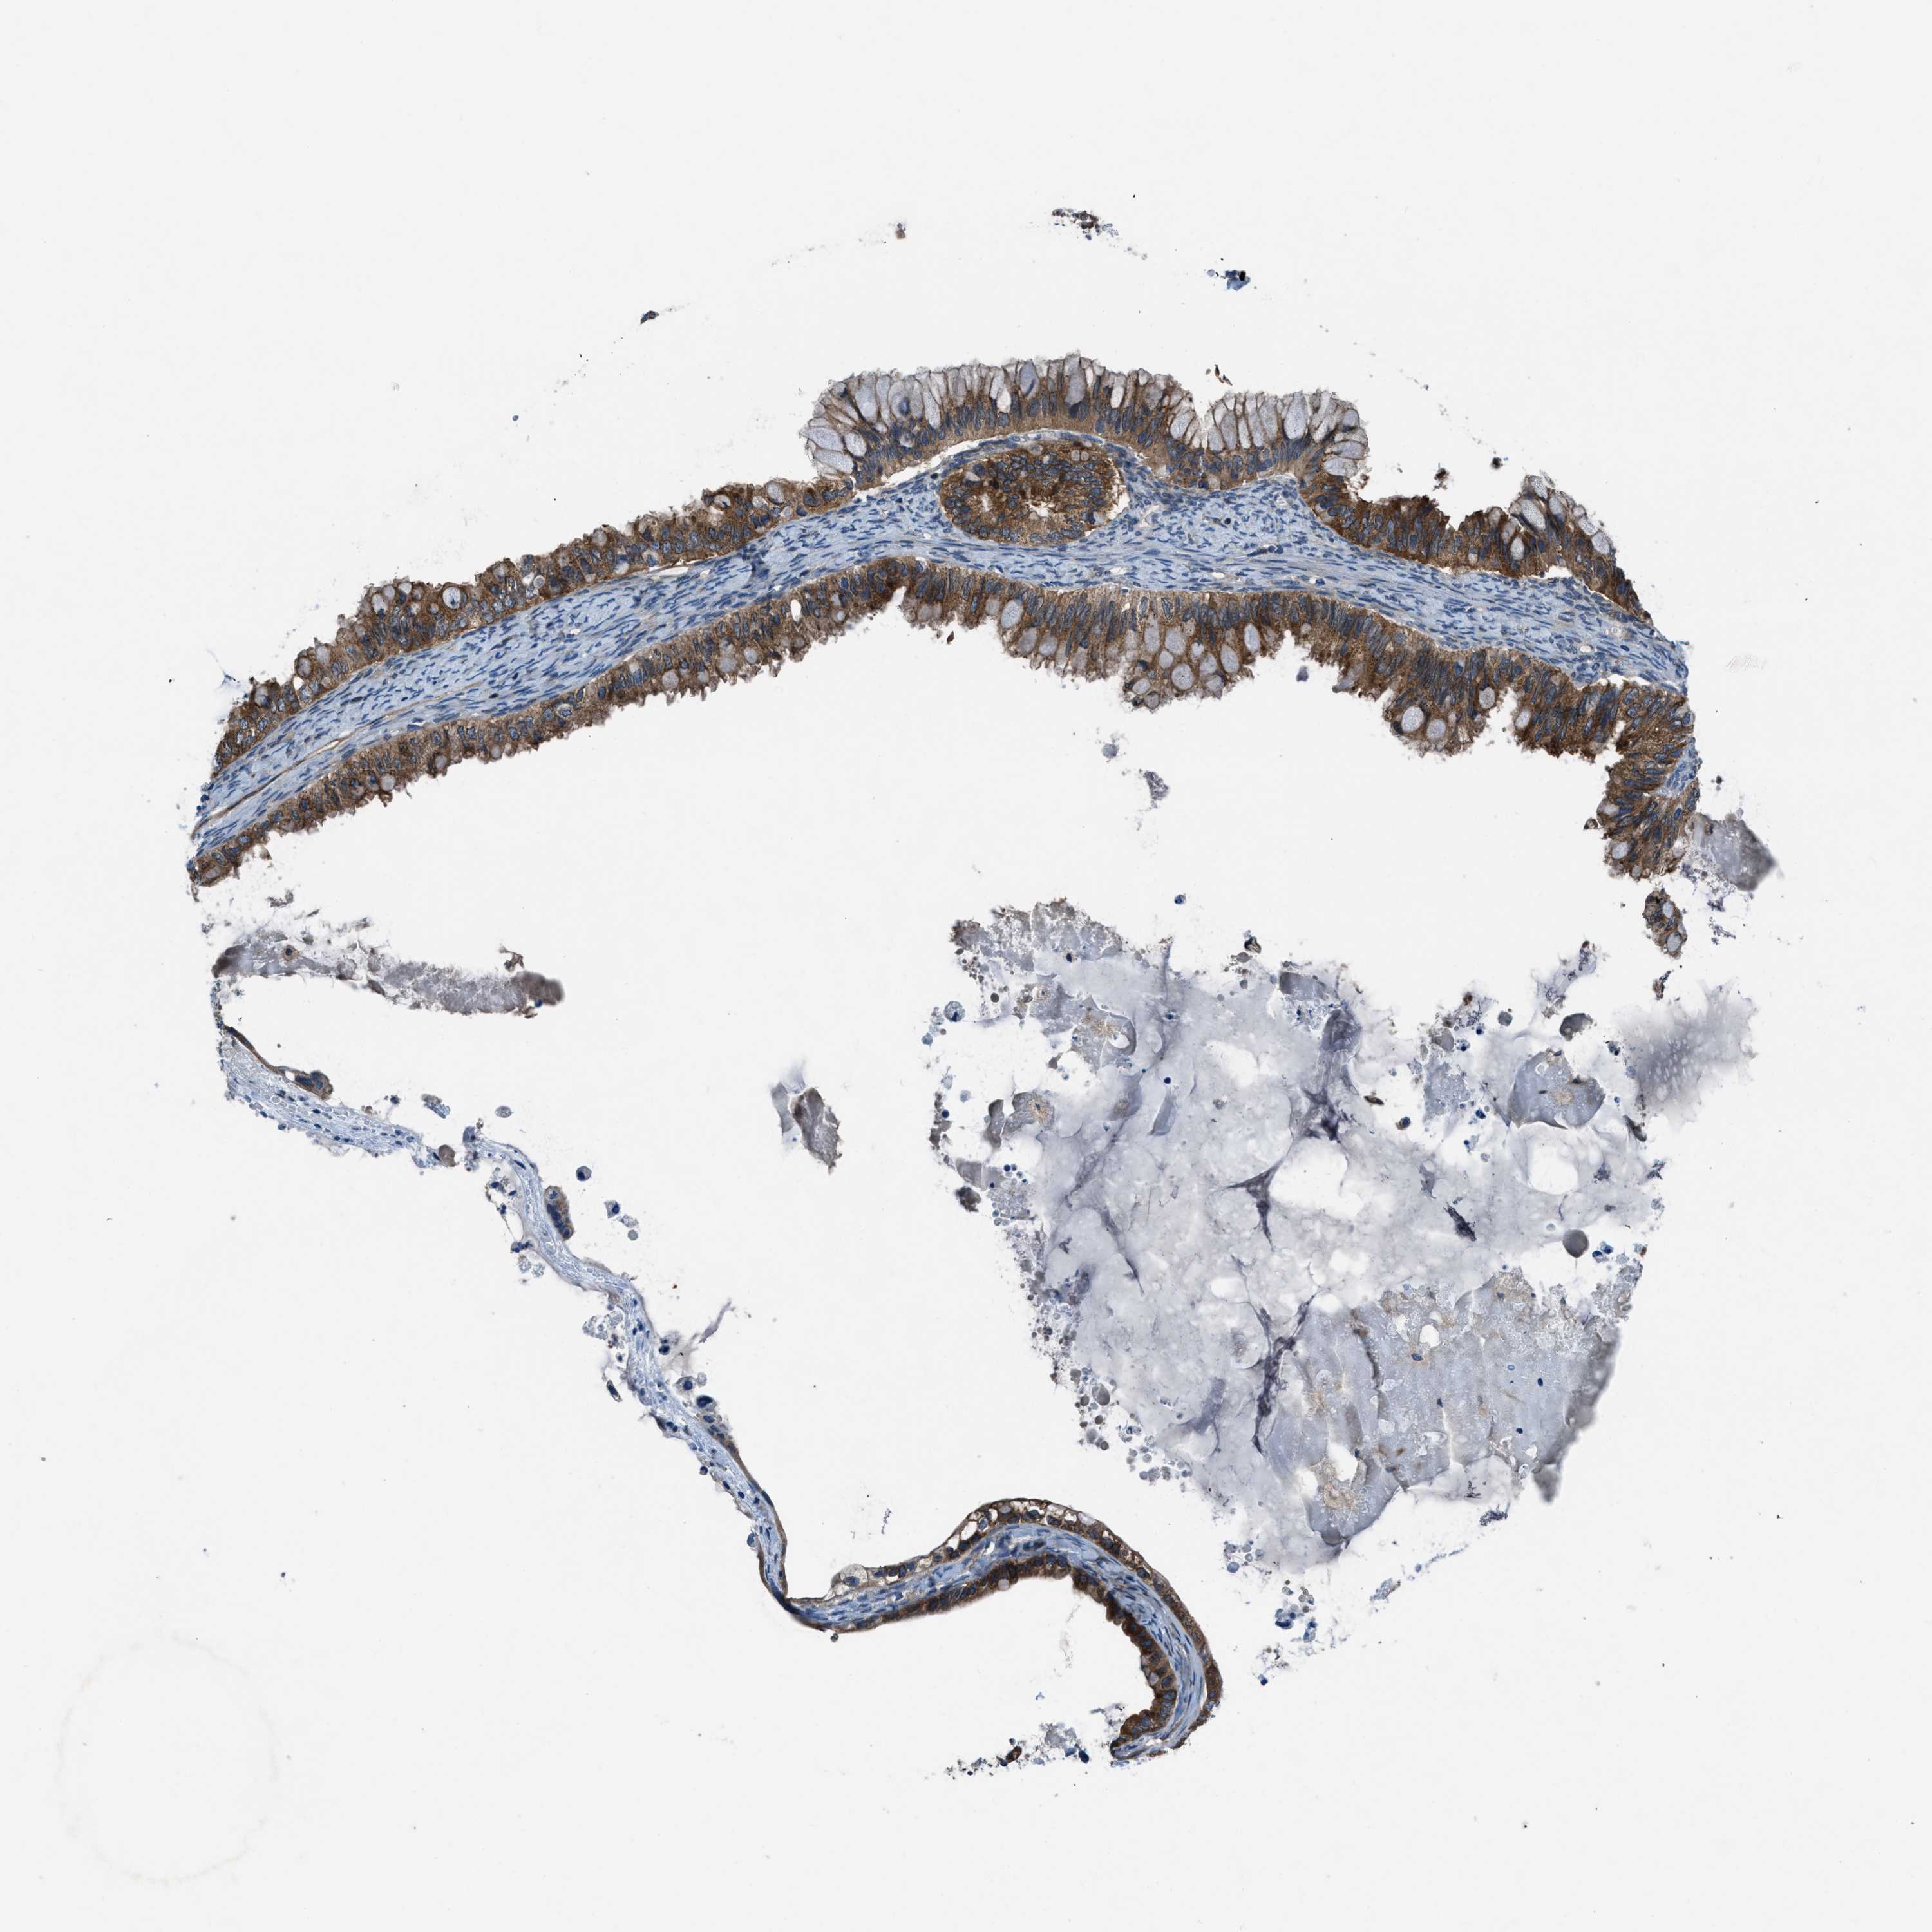

OVARIAN CANCER - Protein expressioni

A mouse-over function shows sample information and annotation data. Click on an image to view it in a full screen mode. Samples can be filtered based on level of antibody staining by selecting one or several of the following categories: high, medium, low and not detected. The assay and annotation is described here.

Note that samples used for immunohistochemistry by the Human Protein Atlas do not correspond to samples in the TCGA dataset.

Antibody stainingi

Antibody staining in the annotated cell types in the current human tissue is reported as not detected, low, medium, or high, based on conventional immunohistochemistry profiling in selected tissues. This score is based on the combination of the staining intensity and fraction of stained cells.

Each image is clickable and will lead to virtual microscopy that enables deeper exploration of all samples and also displays staining intensity scores, fraction scores and subcellular localization as well as patient and tissue information for each sample.

Antibody HPA016649

Antibody HPA018152

Cystadenocarcinoma, serous, NOS

Carcinoma, endometroid

Cystadenocarcinoma, mucinous, NOS

Carcinoma, NOS